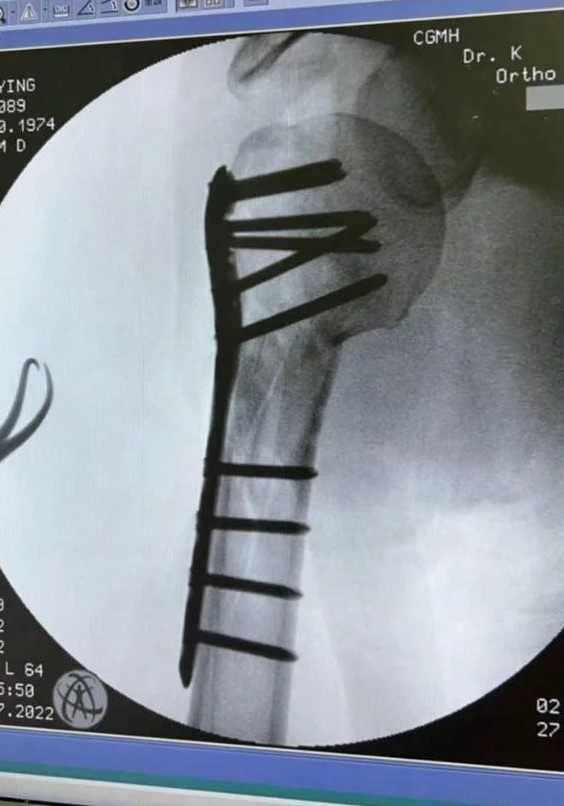

Ngày 15/12, Sina đưa tin Lâm Chí Dĩnh lần đầu tiên công khai chấn thương sau vụ tai nạn xe hơi hồi tháng 7. Anh đăng ảnh chụp X-quang cánh tay sau khi được phẫu thuật. Theo tài tử Thiên long bát bộ, anh được đóng 10 chiếc đinh và một tấm hợp kim titan lên toàn bộ xương để tái tạo cấu trúc và khôi phục cánh tay phải.

Trước đó, Lâm Chí Dĩnh cho biết cánh tay phải của anh bị tổn thương nghiêm trọng. Sau phẫu thuật, anh bị đau nhức triền miên, không thể cầm nắm hay nhấc các đồ vật nhẹ như lược, máy sấy tóc. Nam diễn viên mất một thời gian dài tập vật lý trị liệu mới phục hồi chức năng vận động của cánh tay.

Lâm Chí Dĩnh chia sẻ bệnh án và quá trình phục hồi chấn thương. Ảnh: Sohu. |

Lâm Chí Dĩnh và con trai Jenson gặp tai nạn giao thông tại thành phố Đào Viên ngày 22/7. Vụ tai nạn khiến anh bị vỡ xương mặt, gãy xương bả vai, cánh tay và chấn thương sọ não nhẹ.

Ngôi sao Sợi dây chuyền định mệnh trải qua 3 ca phẫu thuật điều trị. Quá trình phục hồi của nam diễn viên diễn ra thuận lợi, không gặp phải biến chứng. Đáng chú ý, anh vẫn giữ được nét điển trai vốn có sau phẫu thuật tái tạo gương mặt.